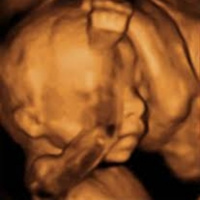

La ecografía de la semana 20 de embarazo30/11/2018 Duración: 53minEn este programa nos centramos en la ecografía más importante del embarazo: la de la semana 20. En esta prueba conoceremos el sexo de nuestra bebé y sabremos si todo marcha bien. Nuestra ginecóloga y nuestra psicóloga nos contarán como afrontar este momento. Además os desvelaremos el origen de las ecografías y entrevistaremos a la responsable de un centro especializado en ecografías en 4D. También os traemos un mami consejo, un ejercicio para manteneros en forma en el embarazo, música y, por supuesto, las respuestas a las preguntas que cada semana nos enviais al consultorio.